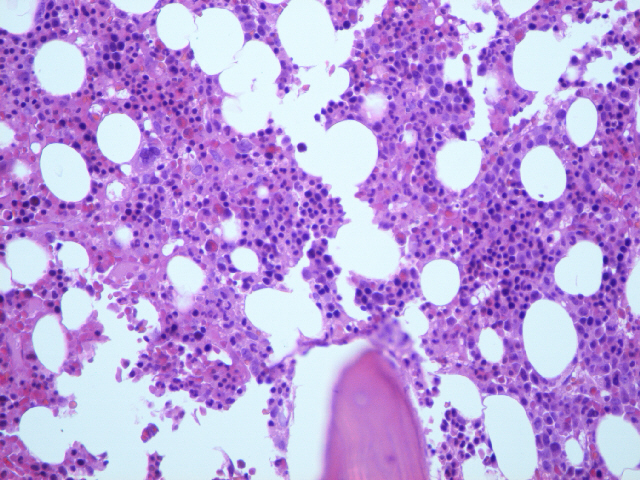

Presentamos cuatro fotografías de una biopsia seccionada por la mitad en cada uno de los cuales se utilizó uno de los métodos expuestos de fijación y decalcificación. Como se puede observar en la muestra fijada en Bouin (fotos 3,4) hay mayor cantidad de material y su calidad también es superior. Pensamos que puede ser debido a una mejor decalcificación y por tanto mayor integridad de la pieza al corte en el microtomo. Esperamos vuestros comentarios, especialmente si teneis experiencia en la aplicación de técnicas inmunohistoquímicas con BMO fijadas y decalcificadas en Bouin.

Fotografía 1: Corte de médula osea fijada en formol-acético. Tinción hematoxilina-eosina.

Fotografía 2: Corte de médula osea fijada en formol-acético. Tinción de giemsa.

Fotografía 3: Corte de médula osea fijada en liquido de Bouin. Tinción de hematoxilina-eosina.

Fotografía 4: Corte de médula osea fijada en liquido de Bouin. Tinción de giemsa.